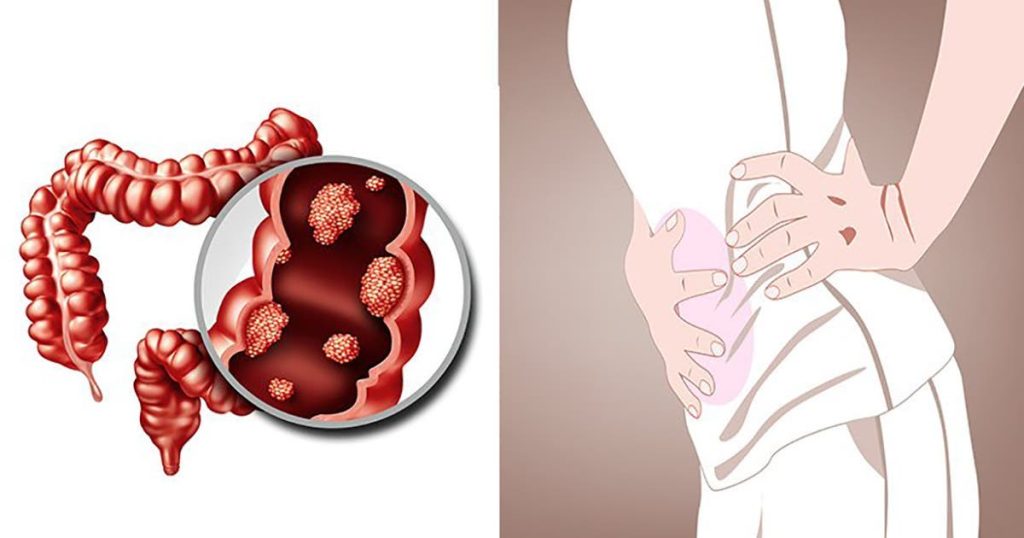

Rak to choroba spowodowana transformacją i nadmierną proliferacją komórek, których geny wynikają z mutacjom lub zmianom. Te następujące elementy są następujące, tzw. guz skutkujący, który może zostać wydany na sąsiednie i narządy. Nazywa się do przerzutami. the profilaktyka, badania przesiewowe i badania kontrolne są niezbędne do monitorowania stanu zdrowia. W przypadku raka grubego (zwanego również rakiem grubego) należy zwrócić uwagę na główne informacje, które dotyczą stadiach rozwoju choroby.

We Francji rak grubego jest częstym zakażeniem u obu płci. Występuje zazwyczaj u osób dorosłych po 50. roku życia, ale może pojawić się w każdym wieku. Jest to teraz rozwijający się z możliwością wystąpienia w jelicie grubym (okrężnicy, jak sama nazwa wskazuje), po wystąpieniu pojawienia się. Jeśli nie zawsze jest zdiagnozowany, gdy wystąpią objawy, objawy nie są zawsze widoczne. Według Kliniki Mayo, cztery główne ostrzeżenia, które należy zwrócić uwagę.